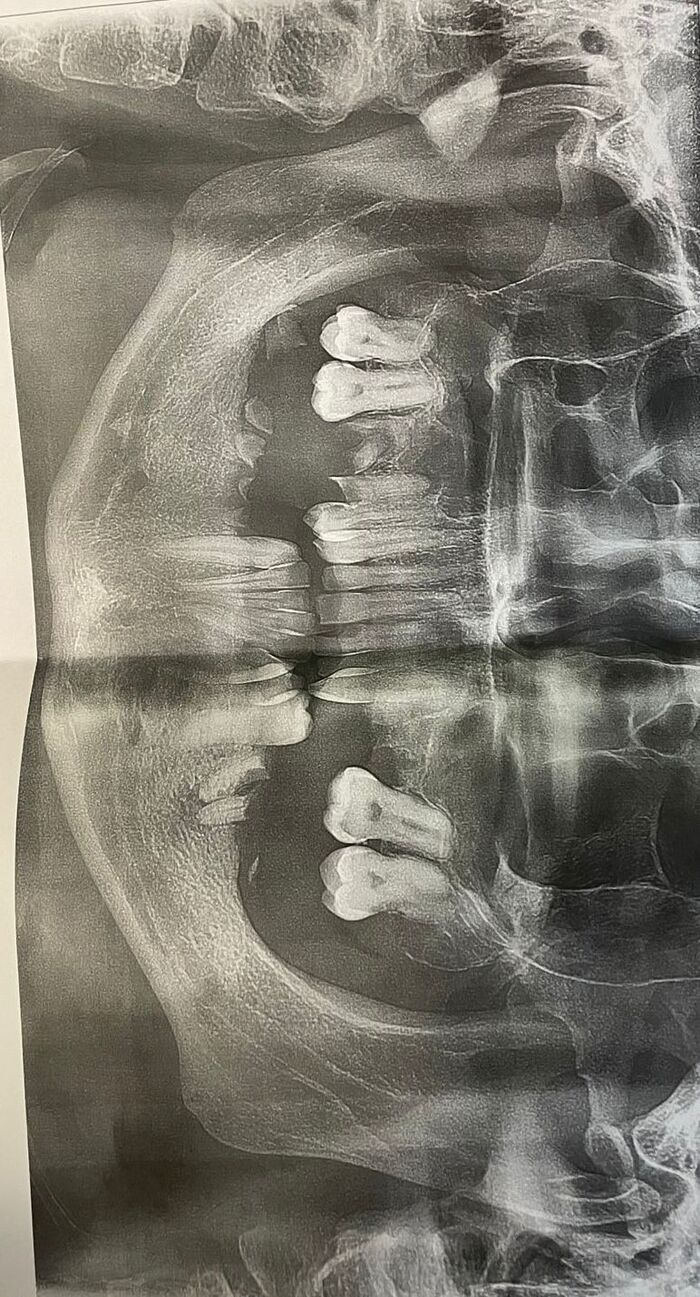

Собственно снимок, так выглядела моя челюсть, на начало лечения.